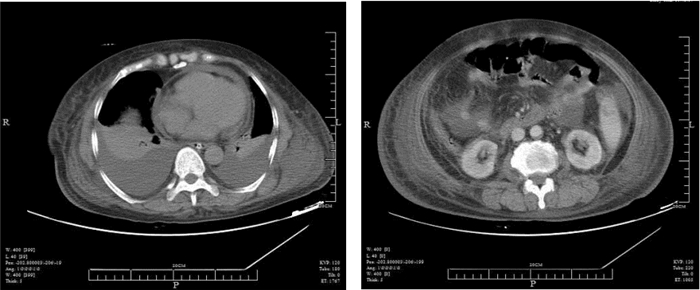

1 病例资料患者,女,64岁,因“反复膝关节疼痛伴腹胀全身肿胀2月余”入院。患者2个月前反复膝关节疼痛后渐出现腹痛腹胀及全身肿胀,及胸闷气急。10 d前至当地医院诊治,给予抗感染、抑酸,营养支持等对症治疗。患者症状无明显好转,遂至本院急诊。既往行“胆囊切除术”后2年,“鼻息肉切除术”后7个月。查体:BP 139/72 mmHg,P:88次/min,R:25次/min,T:37.5 ℃。嗜睡,精神软,口唇无发绀,皮肤干粗糙,巩膜无黄染,全身浅表淋巴结未触及肿大;两肺呼吸低,未闻及干湿性啰音;心率58次/min,律齐,心音低,未闻及病理性杂音;腹膨隆,未见腹壁静脉曲张,腹部可见一长约10 cm手术疤痕,愈合好。未见胃肠型,全腹,左下腹压痛、反跳痛,肝脾触诊不满意,麦式点无压痛,肠鸣音1次/分,腹部移动性浊音阳性;全身浮肿;生理反射存在,病理反射未引出。辅助检查:2012.9.5 肝功(本院):总蛋白 53.2 g/L,白蛋白 24 g/L,尿素 18.41 mmol/L,肌酐 154 μmol/L,血糖 8.74 mmol/L。2012.9.5急诊血常规白细胞 20.6×109/L,中性粒细胞 81.6%,血红蛋白 69 g/L,血小板 22×109/L 。急诊血气分析:pH 7.360,二氧化碳分压. 29.0 mmHg,氧分压. 126.0 mmHg,剩余碱.-8.0 mmol/L;2012.8.28 CT(当地医院)示:两侧胸腔积液伴两下肺压迫性肺不张,心包少量积液,腹腔盆腔积液,肝脏密度不均匀,脾脏增大(图 1,图 2)。2012.8.29 B超(当地医院)示:腹腔积液,双侧胸腔积液(图 3,图 4)。血补体C3 0.472 g/L(0.85~1.93),补体C4 0.077 g/L(0.12~0.36);血T3 0.28 μg/L(0.61~0.81),T4 13.60 μg/L (45~109),FT3 0.70 pmol/L(3.5~6.5),FT4 5.38 pmol/L(11.5~22.7)TSH6.67(0.35~5.50) TPOAb、TgAb阳性;血C-反应蛋白 36 mg/L;腹水外观血性混浊 李凡氏试验(+) 中心粒20 淋巴细胞50间皮细胞25,蛋白35 g/L,CA125 123 U/mL;风湿免疫功能:ANA,SCL-70,JO-1,U1RNP,SM,SS-A,SS-B,组蛋白抗体,抗线粒体抗体,抗PCNA抗体,板层素抗体,抗肌动蛋白抗体,着丝点抗体,抗核小体抗体,均阴性;凝血全套正常;结核抗体阴性;肿瘤指标CA125 512 U/mL。入院诊断为:原发性甲状腺功能减退、多浆膜腔积液。口服左甲状腺素片50 μg/d为初始剂量,以后逐渐增至150 μg/d,泼尼松5 mg早8:00、晚16:00 口服,患者3 d后食欲好转,查头颅MRI及血垂体功能检测正常,排除继发性甲减,停用泼尼松。半月后浮肿消退,至住院1月复查CA125 20 U/mL;B超:心包积液及双侧胸膜腔积液完全吸收,腹腔少量液性暗区。住院40 d复查甲功正常;B超:肝肾隐窝、脾周及腹腔内均未见游离液性暗区(图 4),临床痊愈,出院,出院后服用左甲状腺素片150 μg/d,定期随访,目前以此剂量维持。

| 图 1 治疗前CT:A 胸腔积液,B 心包积液,腹腔盆腔积液 |